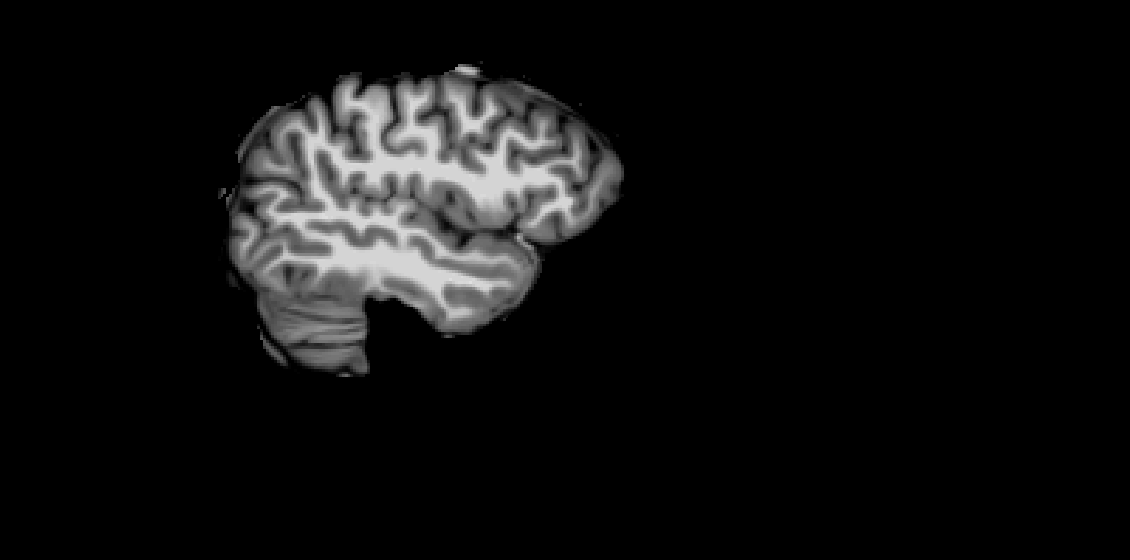

smriprep brain mask